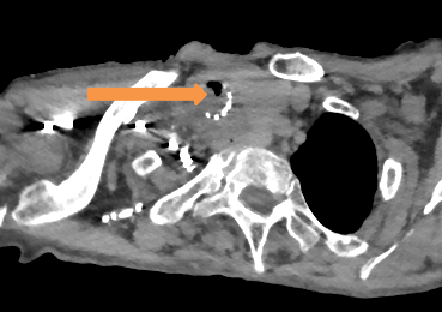

耄耋之年的患者李女士(化名)此前因气道受压曾留置气管支架,尽管原发病治疗取得一定效果,但近两周来喘憋症状反复加重,日常活动及平卧休息均受影响,辗转前来清华大学附属垂杨柳医院胸外科寻求帮助。在接诊后,胸外科团队为患者迅速完善了相关检查,胸部CT及肺功能检测发现患者气道狭窄位置位于原有气管支架旁,因组织增生导致气道严重堵塞。

▲术前CT(箭头处为气道最狭窄处)